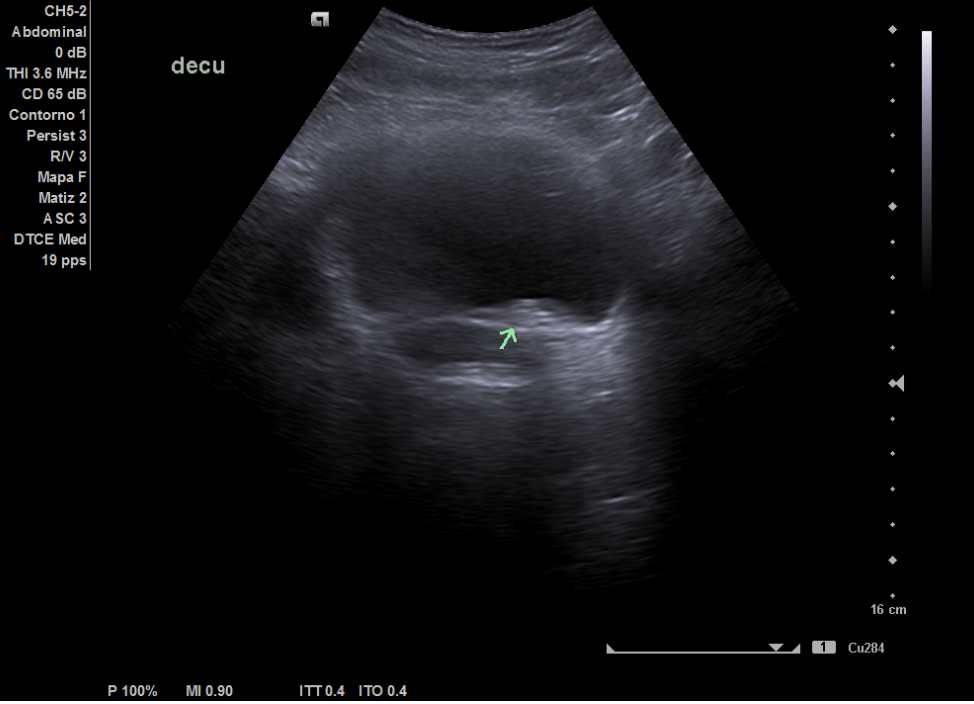

Ecografía: hígado de tamaño y ecoestructura normal, sin evidenciar masas focales. No se aprecia dilatación de las vías biliares. Vesícula sin litiasis. Páncreas visualizado parcialmente, sin evidenciar masas. Bazo de tamaño y ecoestructura normal. Los riñones son de tamaño, forma y ecoestructura normal, con buena diferenciación parénquima-seno y grosor cortical conservado, sin dilatación de vías excretoras ni clara imagen de litiasis. Vejiga distendida de aspecto normal, visualizando dudosas litiasis en las uniones vesico-ureterales.

La ecografía en el centro de salud permitió descartar dilatación pielocalicial o litiasis renal y orientó el diagnóstico hacia posibles secuelas del tratamiento endoscópico previo (STING), mejorando el manejo de la paciente en Atención Primaria. Además, aceleró los tiempos diagnósticos al posibilitar la solicitud de un TAC y una derivación más dirigida al especialista en Urología. Finalmente, cabe destacar que todo ello conlleva a la mejora de la relación médico-paciente.